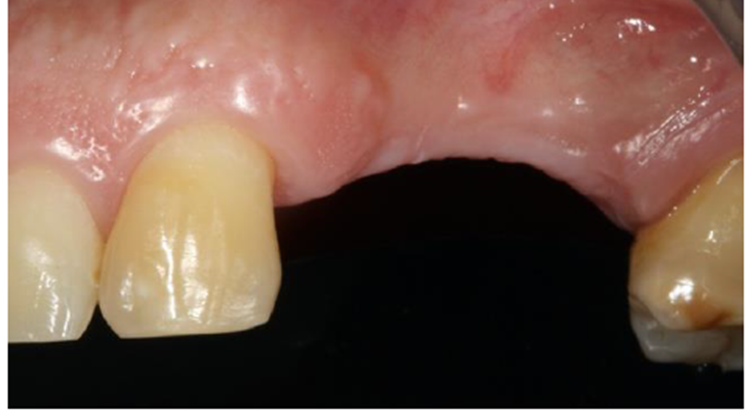

Paciente do gênero masculino, com 52 anos, procurou o curso de cirurgia avançada para Implantodontia UNISUL-SC, buscando reabilitação com implantes na região posterior esquerda da maxila, relatando ter pedido os dentes há aproximadamente 20 anos (Figuras 1 e 2).

Durante os exames de imagem foi observado que o paciente apresentava uma atresia em espessura, impossibilitando a instalação dos implantes em posição ideal.